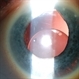

- lens, dislocated lens

- Lens dislocated into the anterior chamber.